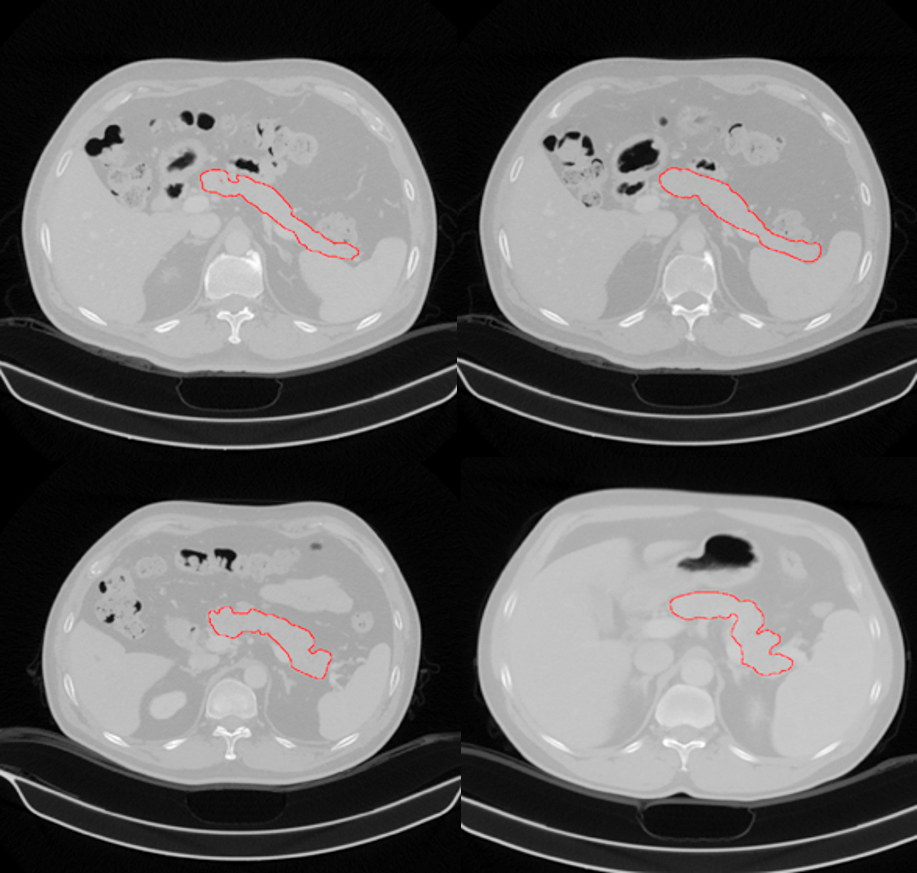

描紅部分為王一達團隊找出的胰腺位置